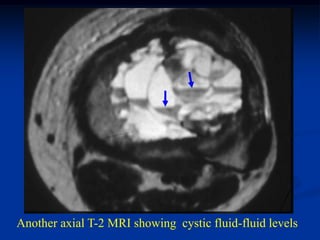

Another axial T-2 MRI showing cystic fluid-fluid levels

Axial T-2 MRI